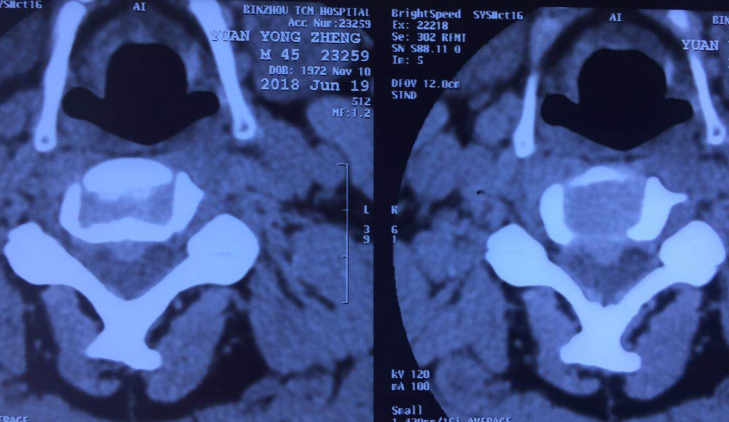

术前CT